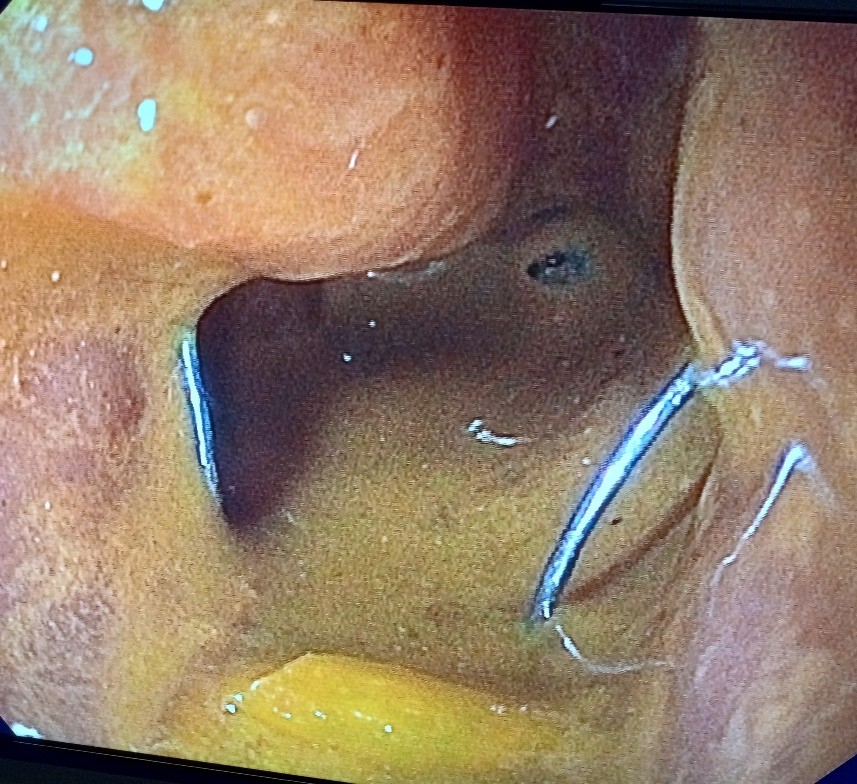

Colonic stent placement was performed under general anesthesia. The patient was placed in the left lateral decubitus position and a double channel therapeutic gastroscope (Olympus America) was passed into the rectum until an area of complete colonic obstruction was reached in the sigmoid colon. The fluoroscopy was also used in this procedure. The luminal obstruction was so severe we have to use ERCP cannula and 0.025 in angled visiglide wire (Olympus America) under fluoroscopy to access the obstructed proximal part of the dilated colon through the tumor. Then a 25 mm x 90 mm Boston Scientific colonic stent was deployed (Figure5) successfully, and stool was visualized coming through the stent from the obstructed part of the colon (Figure 6). A follow-up x-ray of the abdomen was used to confirm there was no adverse event like perforation (free air under the diaphragm).

Figure 4. Malignant obstruction in the sigmoid colon prior to stent placement.

Figure 4